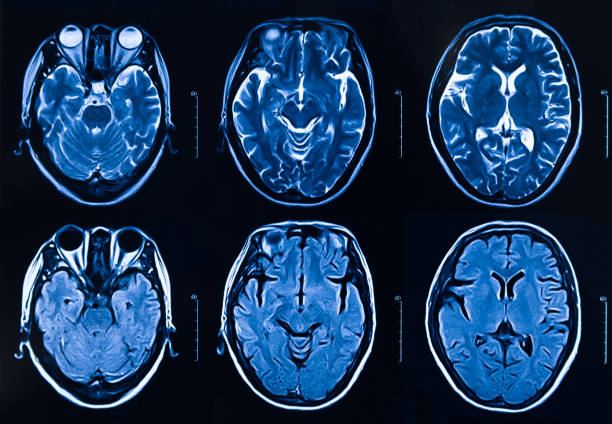

이런 뇌졸중 전조증상들을 알고 확인했더라도 제일 중요한 것은 바로 뇌졸중 치료가 가능한 상급병원으로 이송하는 것이 가장 중요합니다. 미국 심장뇌졸중학회에서 이야기하는 FAST는 Face, Arm, Speech, Time 약자로 위에서 언급한 증상을 확인시 3시간 이내에 응급실로 가야만한다고 골든타임을 제시하고 있습니다.

골든타임은 아무리 강조해도 정말 중요한데 특히 뇌졸중에 있어서는 주로 허혈성뇌졸중, 뇌경색 등 막힌 혈관인 경우 해당사항이 많은데 뇌혈관이 막히고 3시간에서 4시간 반이 지나면 혈전용해제라는 치료가 불가하기 때문에 빠른 시간 안에 뇌졸중 치료가 가능한 상급병원을 확인하고 이송하는 것이 가장 중요합니다.

골든타임 안에 환자가 병원에 도착한다면 환자 상태에 따라 혈전용해제 투여를 시도하는데 작은 혈관이 아닌 큰 혈관이 막혔다면 이는 기계적으로 혈전을 제거하기 위해 시술을 시행할 수 있으며 이 역시 환자 뇌 상태에 따라 24시간 이내에 치료가 가능한 것으로 알려져 있습니다. 뇌출혈의 경우에는 바로 환자 의식이 저하되기 때문에 자발 호흡이 어려울 정도로 상태가 악화 되어 있다면 응급수술이 필요한 경우도 있기 때문에 그 원인에 따라 뇌혈관 기형 혹은 뇌동맥류 파열 등이 확인된다면 이에 맞는 치료를 시작하게 됩니다. 이러한 급성조치가 지나고 어느 정도 회복을 한 환자는 뇌경색이나 뇌출혈로 있는 뇌부종이 가라앉는다면 사회 복귀하기 위한 재활 치료를 병행하는 것이 중요한 것으로 알려져있습니다.